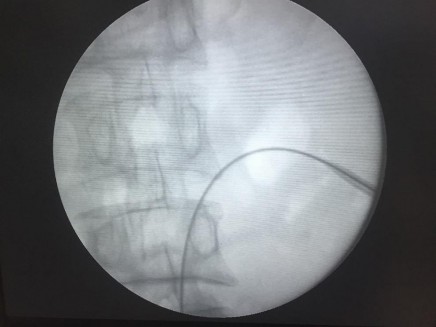

Hình 2.9. Đưa dây dẫn đường vượt qua viên sỏi (mũi tên) dưới kiểm soát của màn hình tăng sáng.

(Nguồn: chụp tại Bệnh Viện Trường Đại Học Y - Dược Huế)